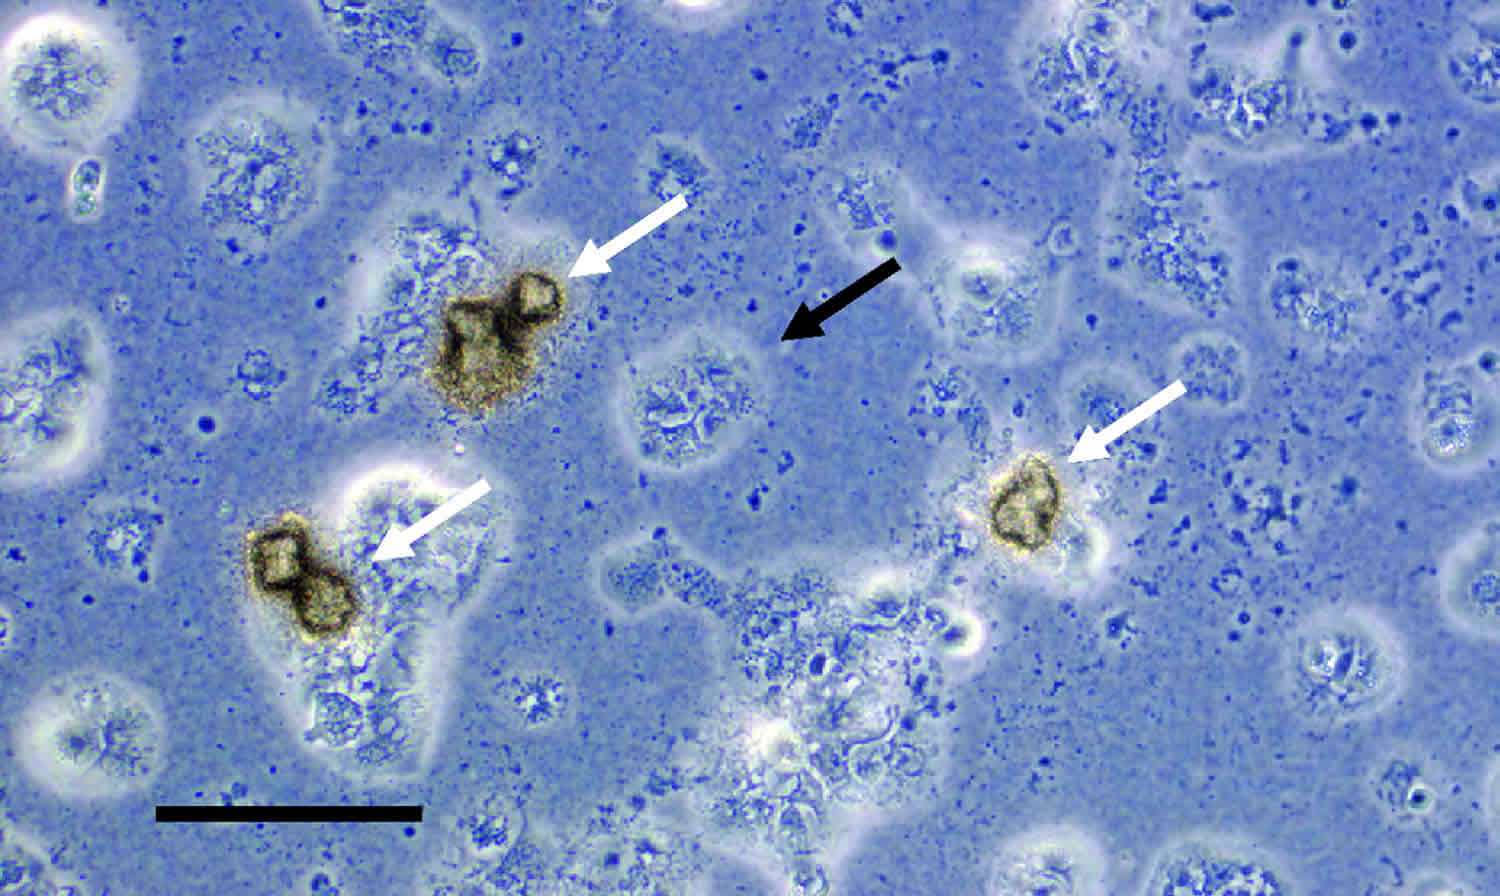

진단 방법

유레아플라즈마 감염은 소변 검사를 통해 진단됩니다. 결과는 대개 3~7일 이내에 나옵니다.